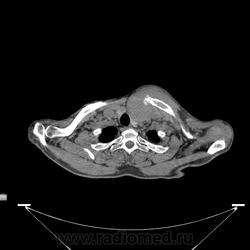

Миелома (плазмоцитома).

Недавний случай. Подтвержден гистологически.  По сцинтиграфии дополнительные очаги гиперфиксации РФП с некоторых ребрах и крестцово-подвздошных сочленениях.